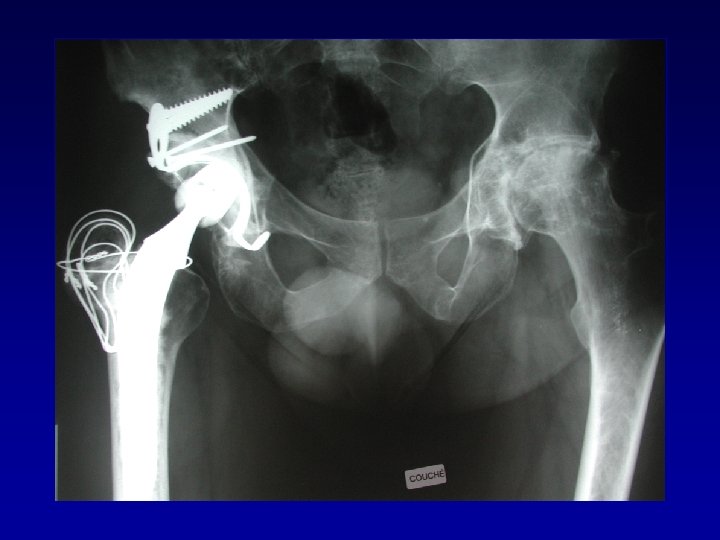

Chirurgie préalable Le matériel en place • Gêne le creusement, la reconstruction Les complications

Chirurgie préalable Le matériel en place • Gêne le creusement, la reconstruction Les complications • Nerveuses : sciatique, crural, fessiers (EMG) • Infectieuses

Arthroplastie totale de hanche sur fracture du cotyle complexe (LCH) • Voie d’abord par

Arthroplastie totale de hanche sur fracture du cotyle complexe (LCH) • Voie d’abord par TROCHANTEROTOMIE Libération de la fibrose, capsule, cicatrices • Permet : Exposition Récupération de la longueur Mobilité